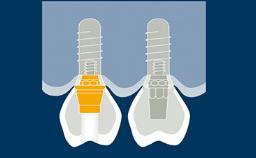

Implant-supported fixed dental prostheses aim to provide replacements for missing teeth that are able to withstand functional demands and accurately mimic the esthetics of the missing dental units.

To achieve this goal, the clinician must select the best available materials to meet the challenges posed by the clinical situation.

This module will discuss the dental materials that are available for the manufacture of implant-supported fixed dental prostheses and the basic principles involved in selecting the material that is best suited for each case.